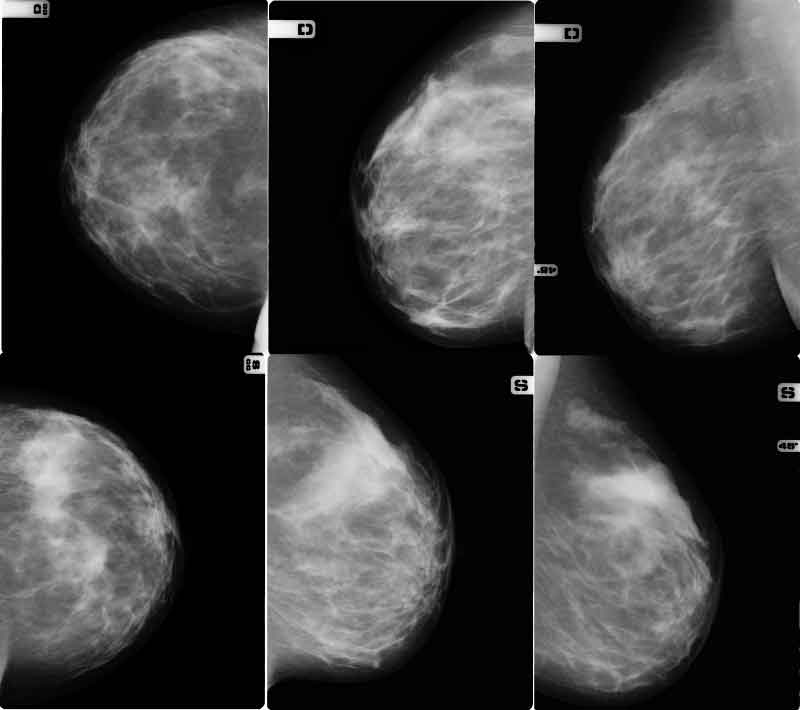

Mammografie: esperti riscontrano sovradiagnosi di tumori innocui

Fino a un quarto dei casi di cancro al seno trovati attraverso mammografie sono innocui e non metterebbero a rischio la vita della donna: e’ quanto rivela un studio norvegese.

Ma ci sono stati almeno 6/10 casi di eccesso di diagnosi, in altre parole in almeno 6/10 casi di diagnosi, quelle donne non avrebbero mai dovuto affrontare una malattia a causa del loro tumore: cifre che si traducono in una ‘sovradiagnosi’ del 15/25 per cento. Le donne, e’ la conclusione dello studio, dovrebbero essere informate sui rischi e i benefici degli screening di cancro al seno, tra cui il rischio di ‘sovradiagnosi’. “Sovradiagnosi e cure non necessarie di cancro non letali creano un dilemma etico e clinico sostanziale e possono mettere in dubbio l’esistenza dei programmi di screening mammografico”, scrivono gli autori dello studio, e dunque almeno le donne dovrebbero “essere adeguatamente informate sul rischio di sovradiagnosi”.